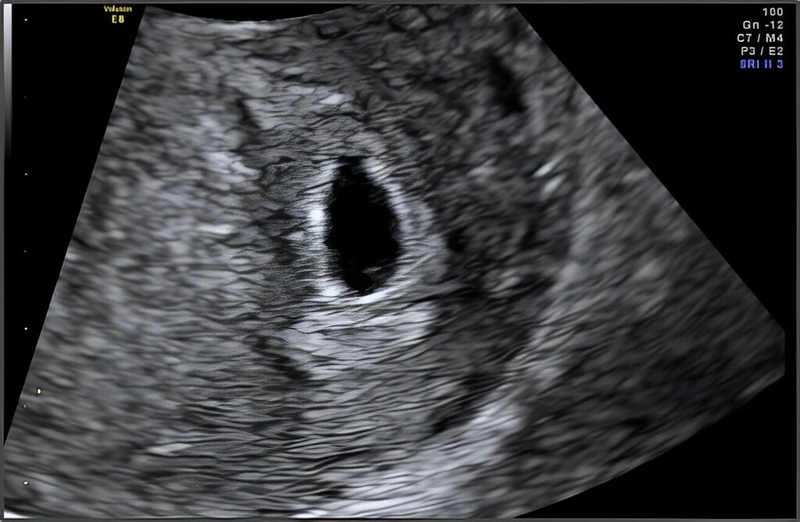

Theo các chuyên gia, khoảng 6 - 7 ngày sau khi trứng được thụ tinh, túi thai sẽ bắt đầu hình thành. Lúc này, nó chỉ là một túi nhỏ, có đường kính khoảng 2 - 3mm. Trong 1 - 2 tuần tiếp theo, túi thai tiếp tục phát triển và lớn dần lên. Đến tuần thứ 4 - 5 của thai kỳ, túi thai sẽ có đường kính khoảng 5 - 6mm. Sau đó, túi thai tiếp tục phát triển và phôi thai bắt đầu hình thành rõ ràng hơn.

Theo các bác sĩ sản khoa, sau khi phát hiện túi thai qua siêu âm, bạn nên đi khám thai lại sau khoảng 1 tuần, muộn nhất là 2 tuần. Lúc này, phôi thai đã phát triển hơn và việc siêu âm sẽ giúp bác sĩ quan sát cấu trúc bên trong phôi thai, xác định tuổi thai và loại trừ nguy cơ mang thai ngoài tử cung. Vậy túi thai 6mm là mấy tuần? Như đã đề cập ở trên, khi túi thai đạt kích thước này thì thường nằm trong khoảng 5 - 6 tuần của thai kỳ. Tuy nhiên, đây chỉ là ước lượng và có thể thay đổi tùy thuộc vào nhiều yếu tố như chu kỳ kinh nguyệt và quá trình thụ thai của người phụ nữ.

Với thắc mắc túi thai 6mm đã có phôi thai chưa thì câu trả lời là “chưa”. Ở tuần thứ 6 - 7 của thai kỳ, phôi thai mới bắt đầu hình thành và phát triển bên trong túi thai. Lúc này, phôi thai chỉ là một khối nhỏ, có đường kính khoảng 0.5mm. Nếu mẹ mới trễ kinh và siêu âm lần đầu cho thấy túi thai 6mm nhưng không có phôi thai thì có thể là bình thường. Tuy nhiên, nếu mẹ đã siêu âm nhiều lần mà kích thước túi thai không thay đổi, có thể thai không phát triển. Trong trường hợp này, mẹ nên theo dõi bằng cách siêu âm mỗi tuần để kiểm tra xem túi thai có phát triển thêm hay không.